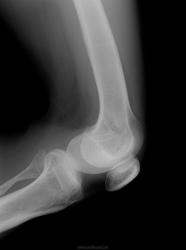

Заключение Главного детского хирурга ДЗ г.Москвы от 02.04.2007 года: Сирингомиелия. Патологический перелом Л2. Кифотическая деформация позвоночника. Радикуломиелопатический синдром. Врожденная сенсорная нейропатия с ангидрозом и спонтанным ангиолизисом. Вальгусная деформация правого коленного сустава на почве остеолизиса дистального мыщелка бедренной кости, нестабильность коленного сустава справа. Плоско-вальгусные стопы.

В неврологическом статусе: Сознание ясное, контактна, ориентирована. Менингеальных знаков нет. Умеренное когнитивное снижение. Несколько эйфорична. Речь дизартричная (неправильный прикус). ЧМН: без патологии. Парезов не определяется. Сухожильные и периостальные рефлексы с рук низкие, без разницы сторон. Коленные и ахилловые отсутствуют. Четких чувствительных нарушений не выявлено. Гипотрофия мышц верхних и нижних конечностей, ягодиц. Грубая деформация правого коленного сустава с формированием ложного сустава, отведением правой голени кнаружи под углом 30-40 град, деформация костей стоп, эквинус с 2-х сторон. Укорочение правой ноги на 15см. ходит с опорой на «мыски». Кифоз шейного отдела. Грубый кифоз поясничного отдела с формированием горба. Сколиоз. Мышечный тонус в верхних конечностях не изменен, в нижних конечностях сни жен, больше справа. Гипермобильность в правом тазобедренном суставе. Тазовые функции: не нарушены.